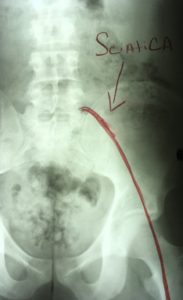

What Causes Sciatica?

True Sciatica is when the sciatic nerve is pinched by either a bulging disc or from a misaligned vertebrae (Subluxation).